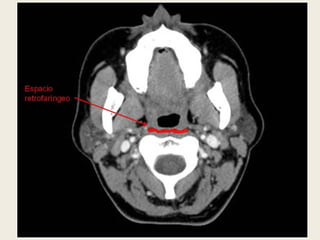

ESPACIO RETROFARÍNGEO

 Se sitúa en la línea media posterior, delimitado

por delante por la capa media de la fascia

cervical profunda, y por detrás y a los lados por la

capa profunda de la fascia cervical profunda.

 Se extiende desde la base del cráneo hasta el

cuerpo de D3.